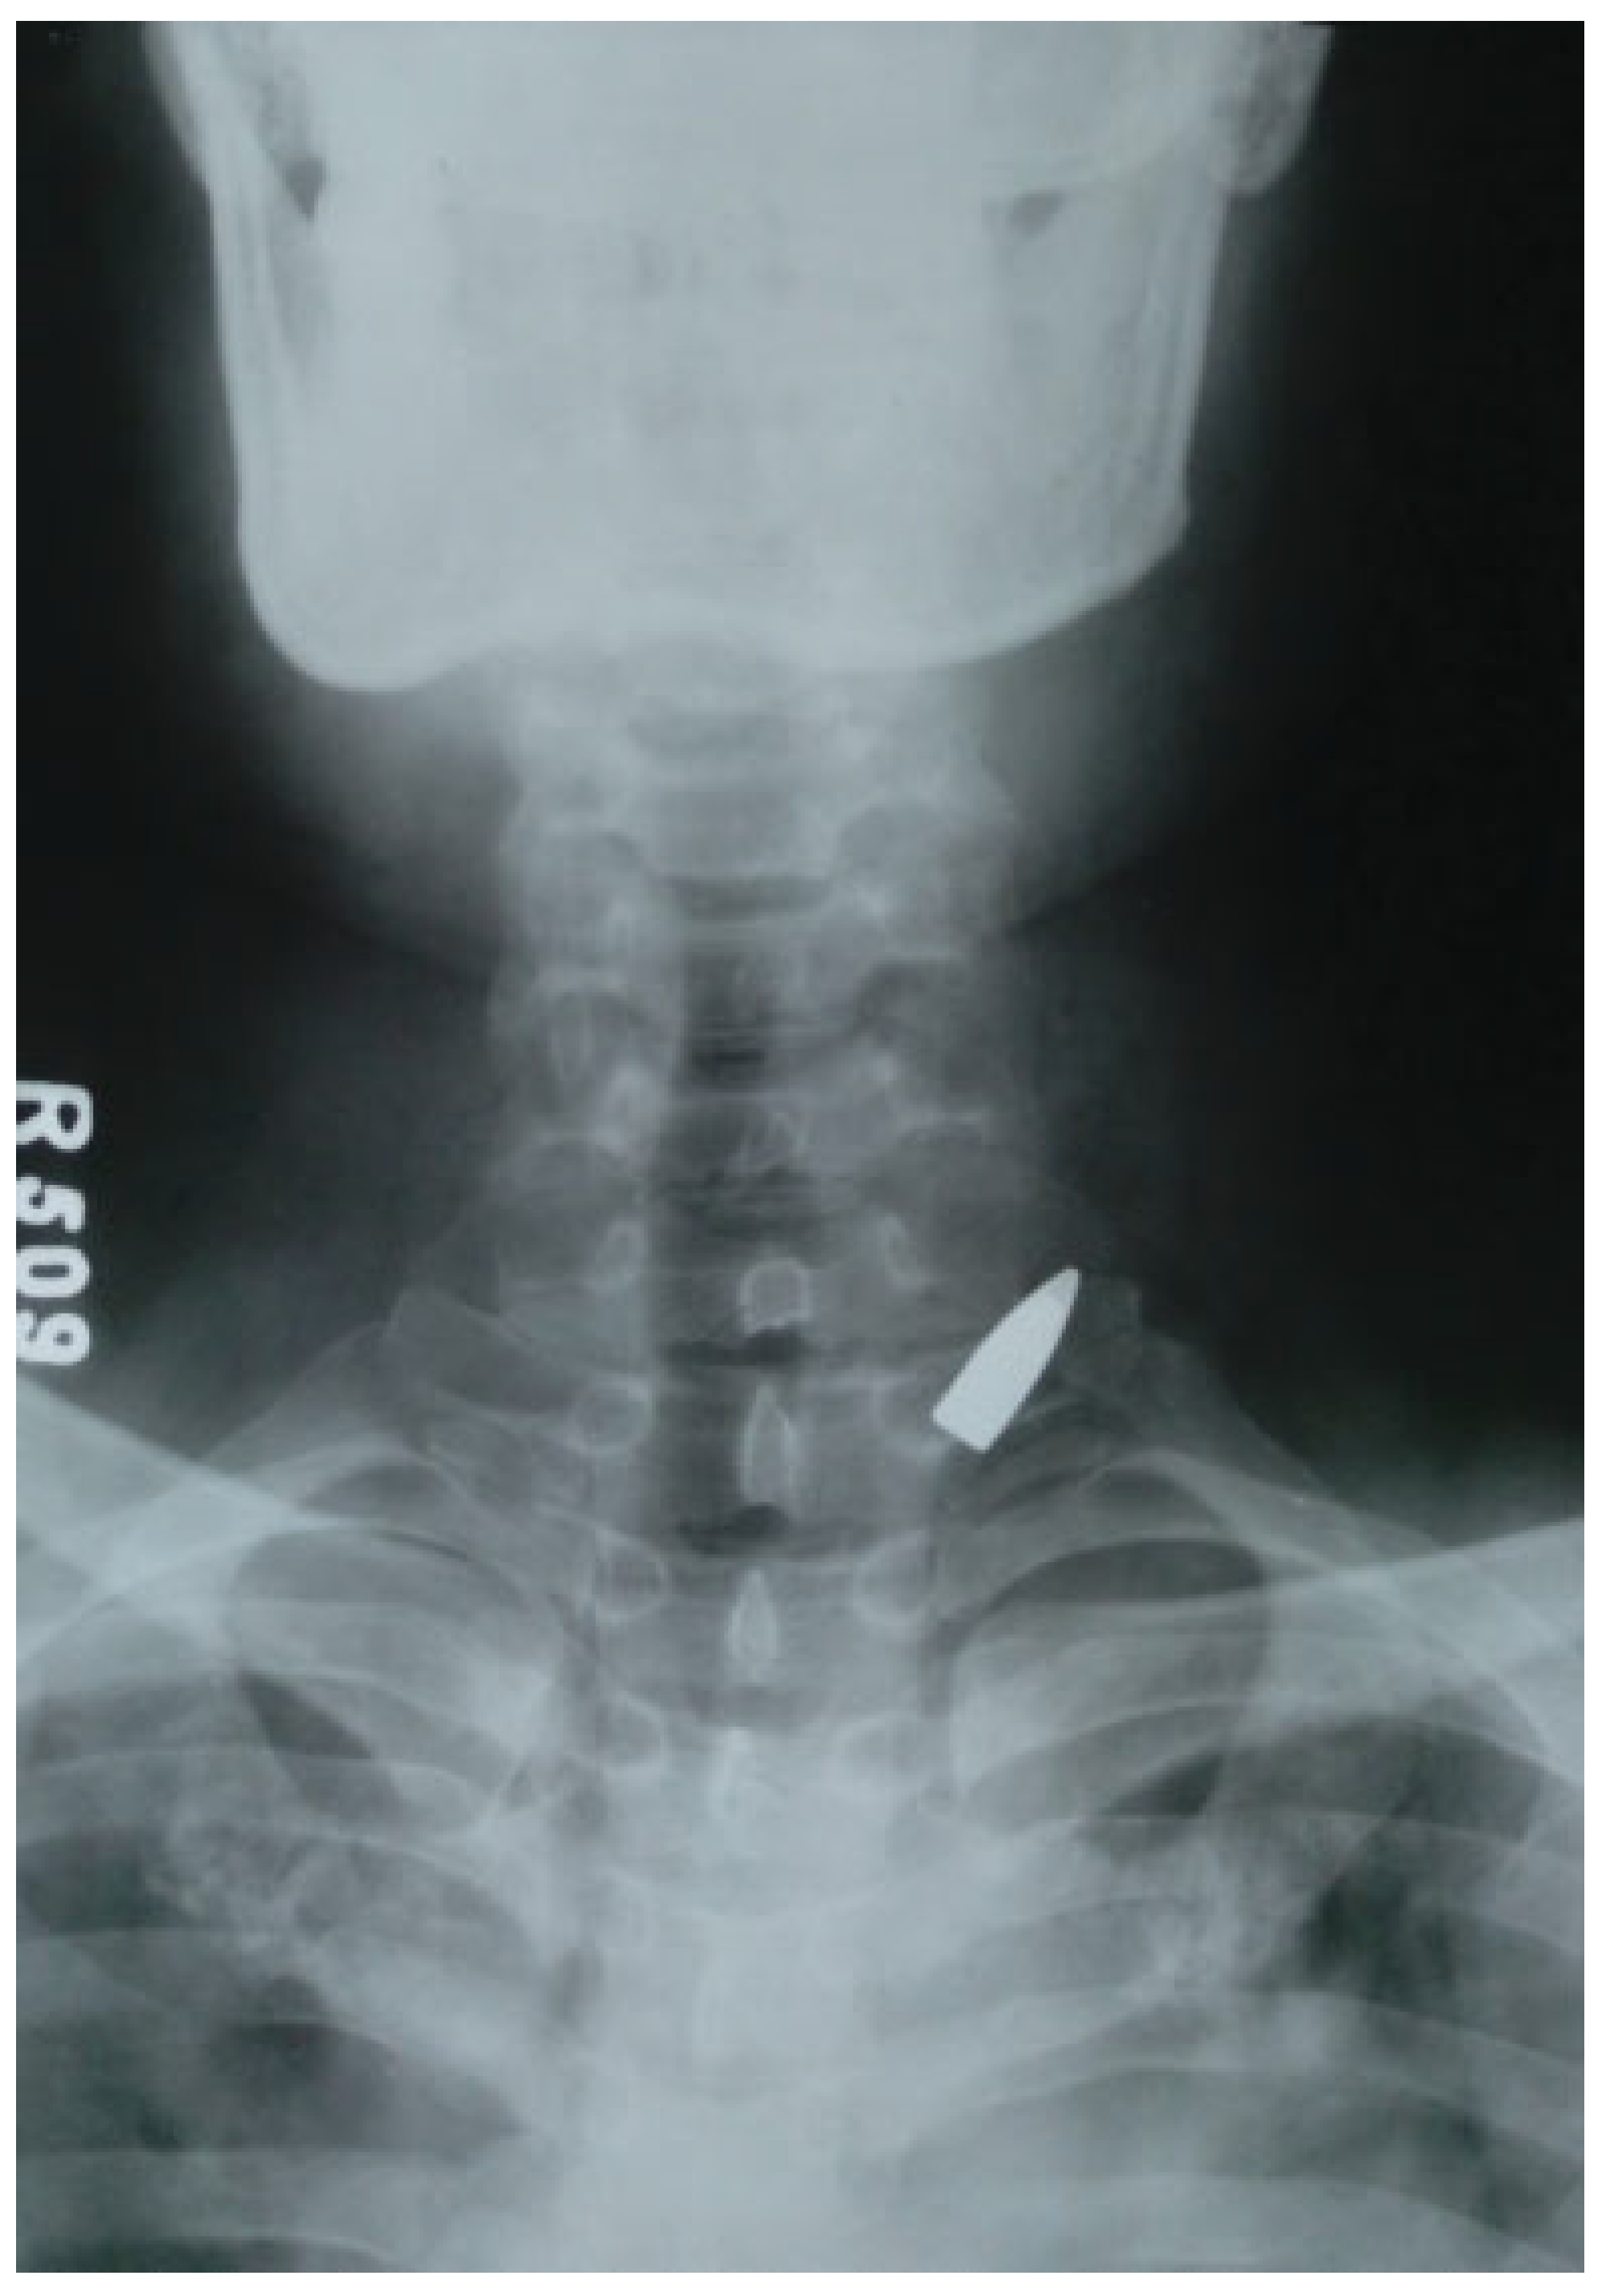

The management of hemorrhage was effective with Foley catheter in 10 out of 11 patients (91%; Figure 1, Figure 2 and Figure 3). One patient who failed to respond had a bullet lodged inside the neck (Figure 4). In this case, the Foley was prematurely removed to prevent further damage to the great vessels. This was followed by management with surgical exploration and repair of internal jugular vein (IJV). Late surgical exploration was done in three cases after CT angiogram for major vessel injury within 24 hours. One case had external carotid injury above the level of facial artery, and the remaining two had IJV injuries. The carotid injury was managed by ligation and IJV injuries were managed by surgical repair by a vascular surgeon. Seven out of 10 cases did not require any intervention for bleeding and the catheter was carefully removed after 72 hours. There was no neurological deficit or complication associated with the use of Foley catheter.

In the present series, the use of Foley catheter resulted in complete elimination of bleeding in 10 patients thereby aiding in hemodynamic stabilization. It also rendered a grace period to carry out CT angiography to rule out major vessel injury within minimum time duration without deteriorating the vitals of the patient. The most important advantage of balloon tamponade is that it requires minimal or no training for its use in emergency scenarios. The average time required for placement of Foley catheter is less than 1 minute. In the present study, we have achieved hemostasis in all our patients but one (n = 10). Nonetheless, the one patient who did not respond had a bullet lodged inside the neck; therefore, the authors had to remove the catheter prematurely to prevent inadvertent damage to the vital structure by the sharp bullet. Furthermore, the case has been managed by open surgical exploration and repair of IJV.

Figure 4. Firearm lodged inside the neck.